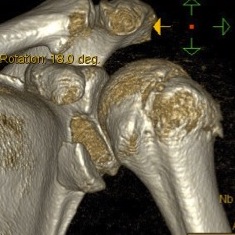

Coracoid process fractures

Scapular process fractures

Types

Coracoid process

Scapula spine

Acromial fractures